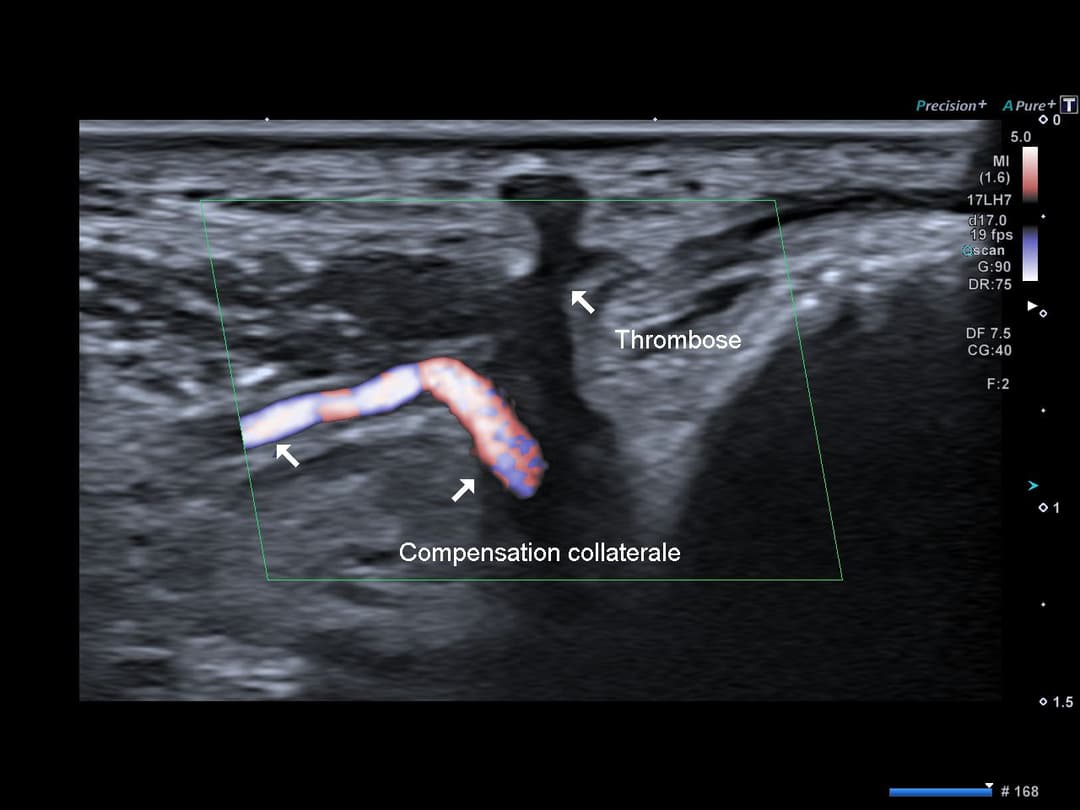

Thrombose complète segmentaire de l'artère radiale avec oedeme péri artériel

En vue longitudinale, visibilité de l'extrémité supérieure de la thrombose avec arrêt du flux en Doppler couleur

Reperméabilisation de l'artère radiale en distalité de la tabatière anatomique par une branche profonde de l'artère ulnaire, venant de l'arcade palmaire dorsale (profonde). L'arcade palmaire superficielle n'étant pas complète chez cette patiente.

Hyperdébit compensateur de cette branche collatérale venant du réseau ulnaire